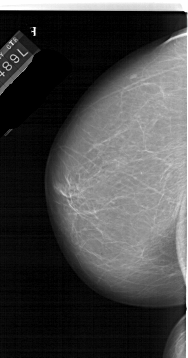

A_1986_1.RIGHT_MLO

RIGHT_MLO LINES 5671 PIXELS_PER_LINE 2851 BITS_PER_PIXEL 12 RESOLUTION 43.5 OVERLAY